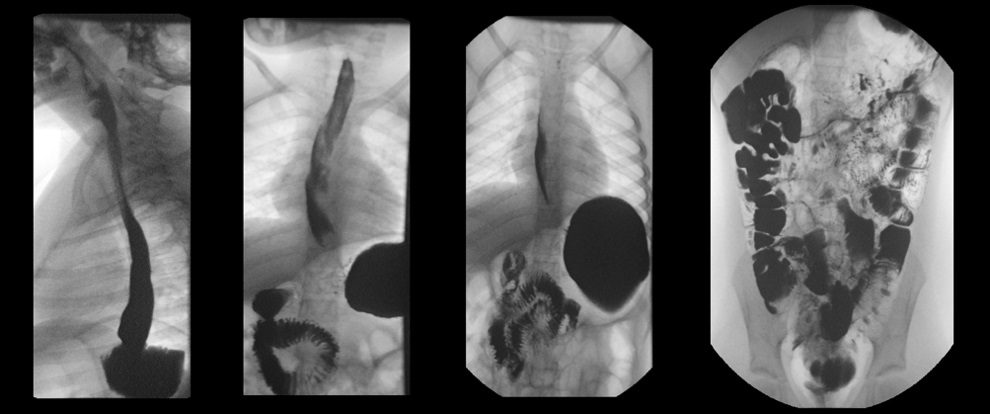

En la exploración física presenta un buen estado de nutrición, con un abdomen marcadamente distendido, timpánico, sin masas ni megalias, no doloroso a la palpación. Se realiza inicialmente radiografía simple de abdomen (Fig. 1), que muestra marcada distensión gástrica y abundante gas en todo el tracto gastrointestinal. Se realiza analítica con hemograma en el que únicamente destaca eosinofilia leve (700 eosinófilos/mm3); bioquímica con perfil hepatorrenal, amilasa y proteína C reactiva normales, hormonas tiroideas y anticuerpos antitransglutaminasa negativos. Estudio de heces con coprocultivo, virus enteropatógenos, toxina de C. difficile y parásitos negativos. Se realiza tránsito baritado (Fig. 2), que muestra marcada distensión gástrica y abundante gas intestinal, con poca motilidad gástrica y paso rápido de contraste a duodeno, sin datos de obstrucción ni vólvulo gástrico. Se completa con una ecografía abdominal sin hallazgos significativos. Tras la realización del tránsito presenta de nuevo importante distensión (Fig. 3), que precisa la recolocación de la sonda nasogástrica. Se produce mejoría clínica tras la descompresión. Se cita en consultas externas para completar el estudio. Se plantea en aquel momento la realización de endoscopia o manometría antroduodenal, para valoración de trastornos de motilidad y la realización de nuevos estudios de imagen como enterorresonancia magnética o incluso laparoscopia exploradora para descartar causa anatómica (vólvulo gástrico intermitente, etc.). El enigma se resuelve a los tres días del alta, tras la expulsión en el contexto de un vómito de un helminto no plano, de 30 cm de longitud, compatible con Ascaris lumbricoides (Fig. 4). Tras la expulsión del nemátodo y la administración de tratamiento con mebendazol oral, presenta buena evolución, manteniéndose asintomática hasta la actualidad.

| Figura 2. Tránsito baritado que muestra distensión e hipomotilidad gástrica con paso rápido de contraste a duodeno, sin datos de obstrucción a ningún nivel |

|---|

![]() |